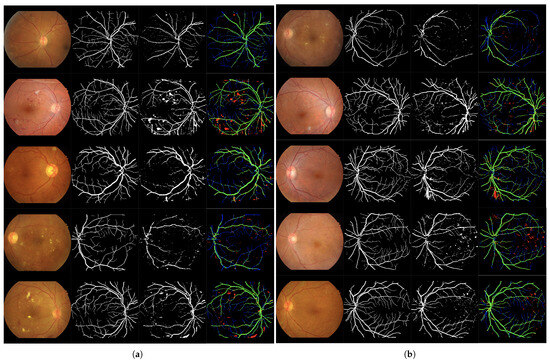

Figure 7.

Set of 4-image sequences illustrating the test results of Experiment 3 graphically. The first image is the original input, the second shows the ground truth vessel locations labeled by experts, the third corresponds to the output of the ANN from experiment 3, and the fourth visualizes the outcome in terms of true positives (green), false positives (red), false negatives (blue), and true negatives (black). Panel (a) displays the first five test images, while panel (b) shows the last five.